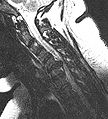

Herniated disc at C6–C7 level

Cervical disc herniations occur in the neck, most often between the fifth and sixth (C5–6) and the sixth and seventh (C6–7) cervical vertebral bodies. There is an increased susceptibility amongst older (60+) patients to herniations higher in the neck, especially at C3–4.[21] Symptoms of cervical herniations may be felt in the back of the skull, the neck, shoulder girdle, scapula, arm, and hand.[22] The nerves of the cervical plexus and brachial plexus can be affected.[23]

• Magnetic resonance imaging (MRI) without contrast is a diagnostic test that produces three-dimensional images of body structures using powerful magnets and computer technology. It can show the spinal cord, nerve roots, and surrounding areas, as well as enlargement, degeneration, and tumors. It shows soft tissues better than CAT scans. An MRI performed with a high magnetic field strength usually provides the most conclusive evidence for diagnosis of a disc herniation. T2-weighted images allow for clear visualization of protruded disc material in the spinal canal.